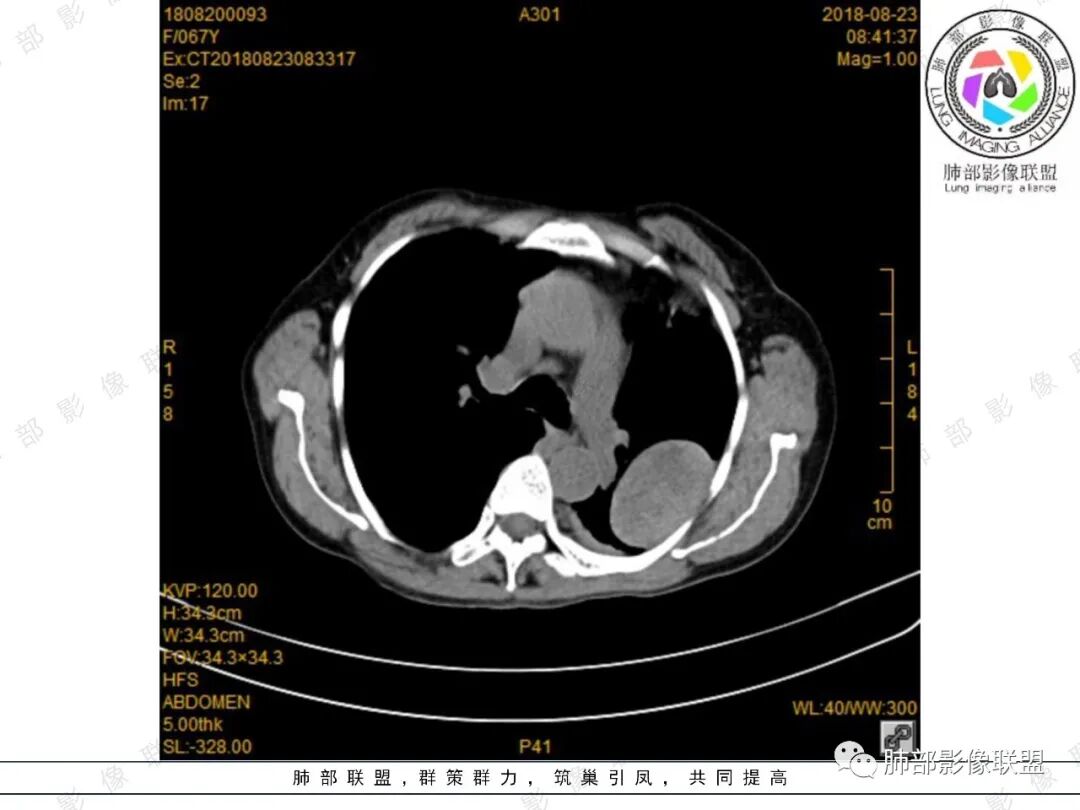

大雄:增强确实看的有些奇怪,胸部的无强化,脾内的轻度强化。如果是EMH,按理有强化的,除非全部脂肪变性了。虽然不是EMH好发位置,但也可以。淋巴瘤强化也不符合,胸部的这个形态也不太像淋巴瘤。如果只是单纯脾大,那么孤立的EMH也很少见。

看图说话:左肺肿块,边缘光滑,密度不均匀,不均匀强化,胸腔少量积液,纵隔肿大淋巴结。脾脏增大,见肿块影,不均匀强化,一元论,考虑淋巴瘤,转移瘤。

大雄:定位肺外  无明显强化  有坏死或囊变   脾大

月亮圆了!:左肺上叶胸膜下肿块,宽基底与胸膜相连,边缘清晰,局部肺组织受压,支气管显示不佳,平扫密度不均匀,增强后,可见轻度不均匀强化,纵隔光滑,无分叶,无毛刺,周围组织无牵拉,收缩,内部有不均匀低密度,脾脏明显肿大,脾内多发类圆形低密度影,增强后,轻度强化,有便血,考虑可能:1:淋巴瘤2:脾梗死。

King:很有意思,能想到髓外造血的老师水平高。首先定位胸膜可能大,倾向良性,渐进强化,脾脏多发占位,渐进延迟强化,两者强化有类似之处,倾向一元论。病灶边缘斑点钙化,淋巴瘤少有。消化道肿瘤转移,胸膜孤立转移少有。恶性孤纤伴脾脏转移,也少。贫血,髓外造血,可以,但胸膜相对少见。副脾,少见部位,强化度差点。总之一元论的话像个少见病变,难以确定,就排个序吧。一元:髓外造血>副脾>淋巴瘤。二元:孤纤+血管瘤/错构瘤.

joyzhy:脾脏占位增大,特点延迟期强化和脾脏一致,考虑血管瘤。胸部占位,考虑肺外,鞘瘤或髓外造血。